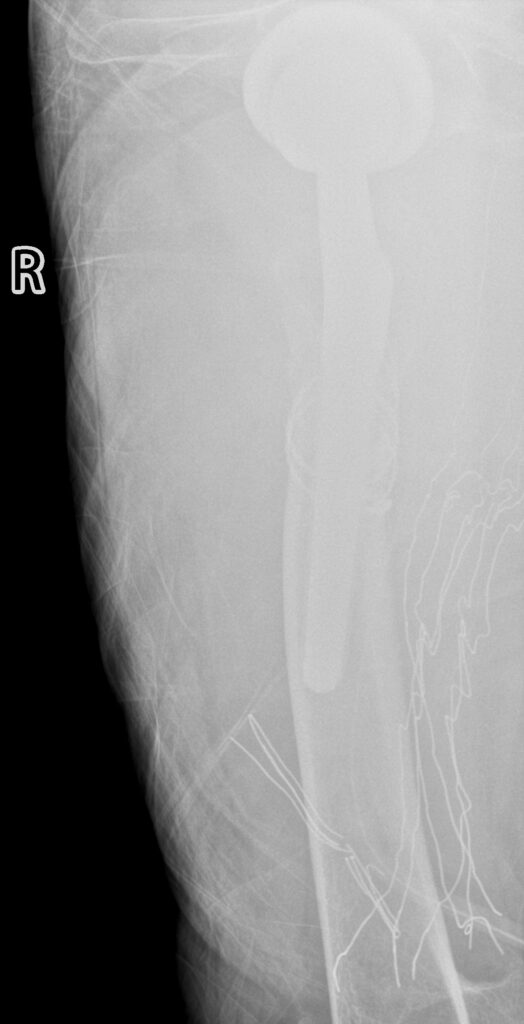

全髋术后股骨侧假体周围骨折切开复位内固定股骨柄翻修术(Open reduction, internal fixation and femoral stem revision for periprosthetic fractures on the femoral side after total hip surgery)